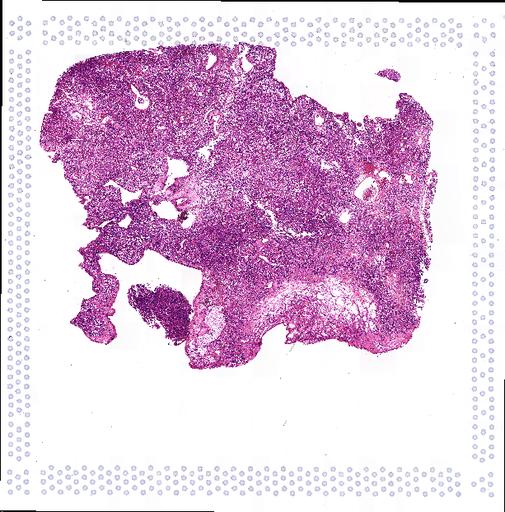

Atlas: Washington University

Identifying tumor-cell-specific markers and elucidating their epigenetic regulation and spatial heterogeneity provides mechanistic insights into cancer etiology. Here, we perform snRNA-seq and snATAC-seq in 34 and 28 human clear cell renal cell carcinoma (ccRCC) specimens, respectively, with matched bulk proteogenomics data. By identifying 20 tumor-specific markers through a multi-omics tiered approach, we reveal an association between higher ceruloplasmin (CP) expression and reduced survival. CP knockdown, combined with spatial transcriptomics, suggests a role for CP in regulating hyalinized stroma and tumor-stroma interactions in ccRCC. Intratumoral heterogeneity analysis portrays tumor cell-intrinsic inflammation and epithelial-mesenchymal transition (EMT) as two distinguishing features of tumor subpopulations. Finally, BAP1 mutations are associated with widespread reduction of chromatin accessibility, while PBRM1 mutations generally increase accessibility, with the former affecting five times more accessible peaks than the latter. These integrated analyses reveal the cellular architecture of ccRCC, providing insights into key markers and pathways in ccRCC tumorigenesis.